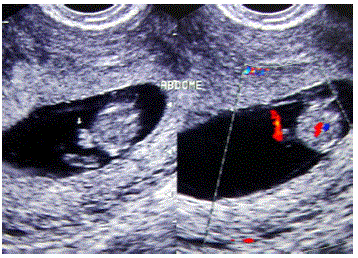

Protrusão do intestino em direção ao cordão umbilical, formando uma herniação fisiológica. De grande importância, pois é responsável pela rotação de 90° no sentido anti-horário que determina a correta topografia do estômago.

Baseado nas imagens disponibilizadas, quando ocorre a rotação adicional completando a rotação da porção medial do intestino?